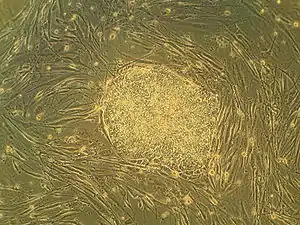

The discovery of insulin at the University of Toronto in 1921 is considered among the most significant events in the history of medicine.[138][139] The stem cell was discovered at the university in 1963, forming the basis for bone marrow transplantation and all subsequent research on adult and embryonic stem cells.[140] This was the first of many findings at Toronto relating to stem cells, including the identification of pancreatic and retinal stem cells.[141][142] The cancer stem cell was first identified in 1997 by Toronto researchers,[143] who have since found stem cell associations in leukemia, brain tumours and colorectal cancer.[144][145] Medical inventions developed at Toronto include the glycaemic index,[146] the infant cereal Pablum,[147] the use of protective hypothermia in open heart surgery[8] and the first artificial cardiac pacemaker.[8] The first successful single-lung transplant was performed at Toronto in 1981, followed by the first nerve transplant in 1988,[148] and the first double-lung transplant in 1989. Researchers identified the maturation promoting factor that regulates cell division, and discovered the T-cell receptor, which triggers responses of the immune system.[149] The university is credited with isolating the genes that cause Fanconi anemia, cystic fibrosis and early-onset Alzheimer's disease, among numerous other diseases.[150] Between 1914 and 1972, the university operated the Connaught Medical Research Laboratories, now part of the pharmaceutical corporation Sanofi-Aventis. Among the research conducted at the laboratory was the development of gel electrophoresis.[151]